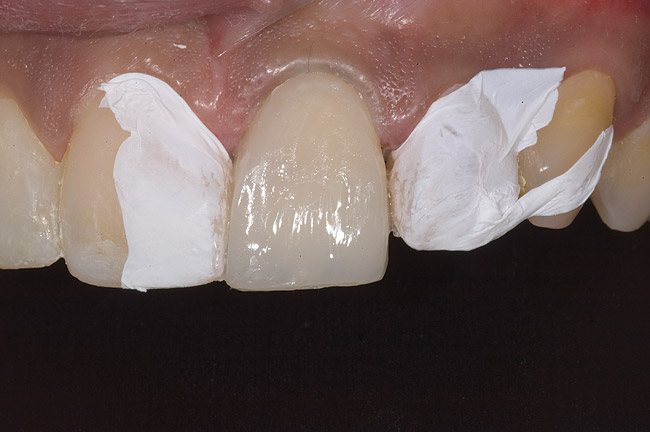

Figure 10  Tooth No. 9 with no preparation on the palatal surface to restore lost form with bonding resin.

Figure 10

Figure 11  Tooth No. 9 with a palatal shelf of nanofilled resin.

Figure 11

Figure 12  Layering dentin shade on tooth No. 9.

Figure 12

Figure 13  Layering enamel shade to full contour.

Figure 13